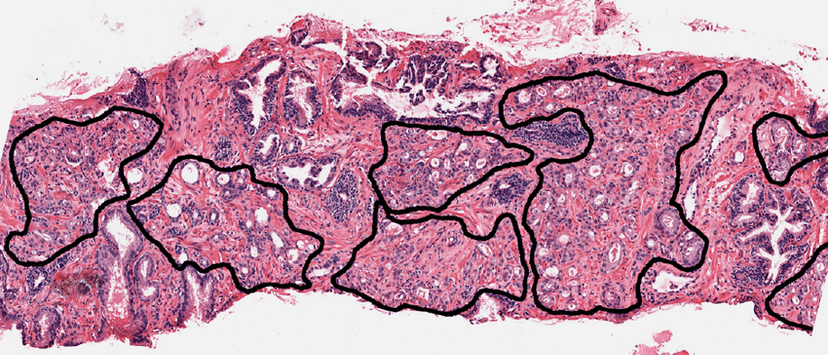

Oncology Pathology Annotation

Comprehensive oncology pathology annotation including WSI slides and tissue/cell level analysis for cancer diagnosis, staging, and research.

- •Whole Slide Imaging (WSI) annotation

- •Tumor region segmentation

- •Cell morphology classification

- •Mitosis counting and scoring

- +10 more capabilities